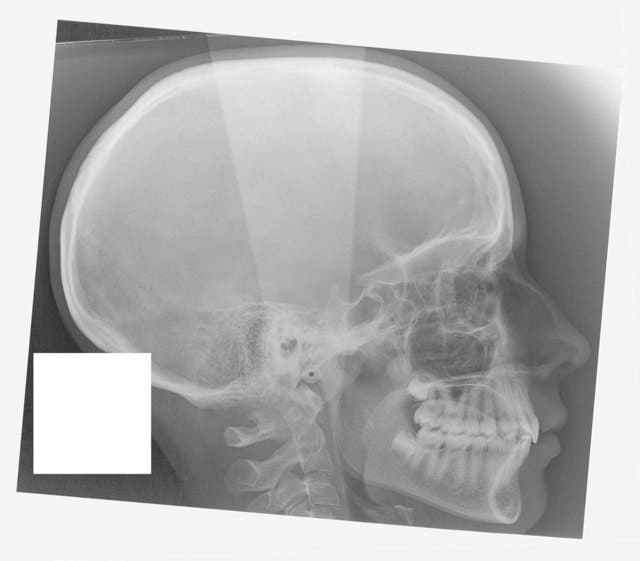

Tele2002 qhiepn - Eugenol

Tele2007 b6yul0 - Eugenol